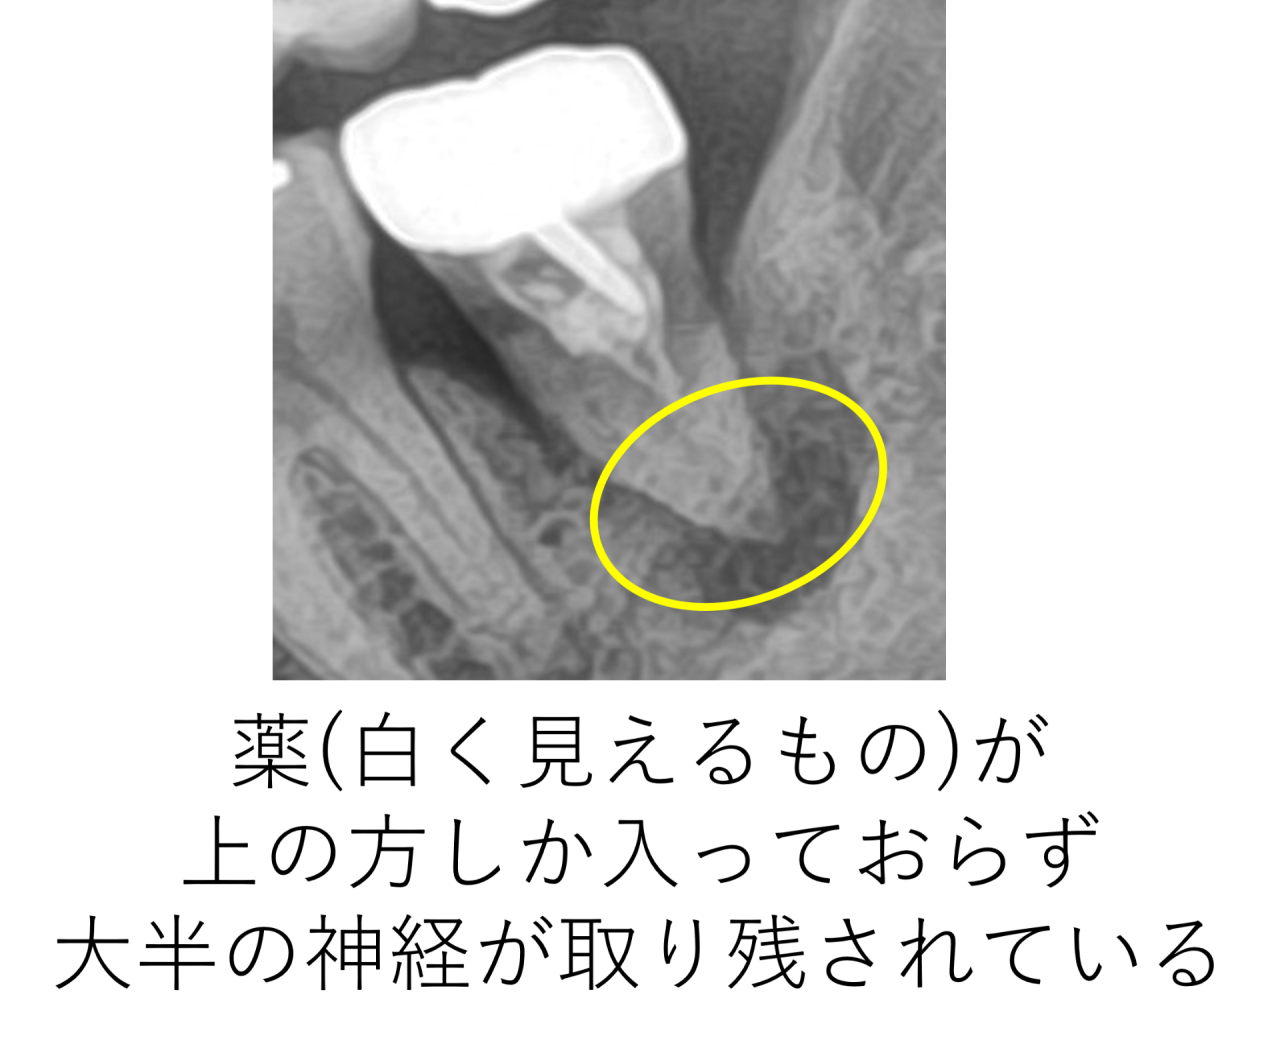

まず、レントゲンを見て予想できることは、以前の治療では顕微鏡(マイクロスコープ)や高倍率ルーペを使わずに肉眼もしくはそれに近い状態で治療したということです。

神経が上の方しか取られておらず、大半が取り残されています。この歯は奥歯の中でも一番奥の歯になります。肉眼ではほとんど見えません。手探りでなんとなくの治療になってしまいます。わからないところは触らずに治療を終わらせるしかないのです。取り残された神経は腐って死んでしまうので、そこから細菌が繁殖し、大きな根の病気を作ります。